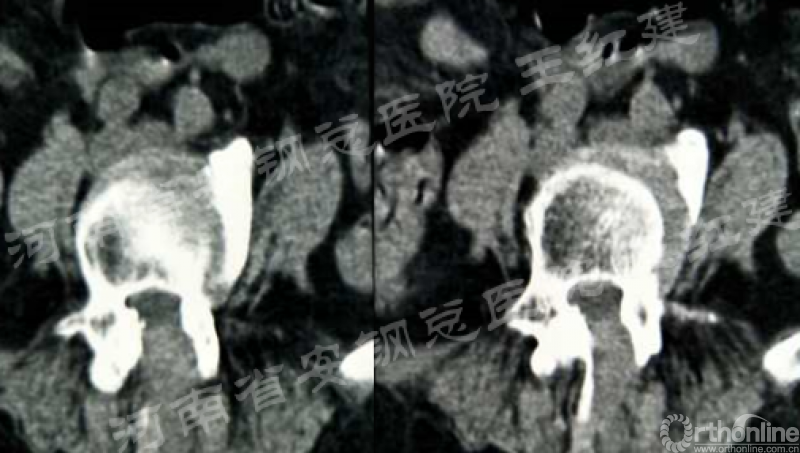

术前

术后

置入内镜通道,用磨钻和枪钳切除上位椎板下缘、下位椎板上缘及突间关节内缘,切除黄韧带,完成单侧入路双侧减压。